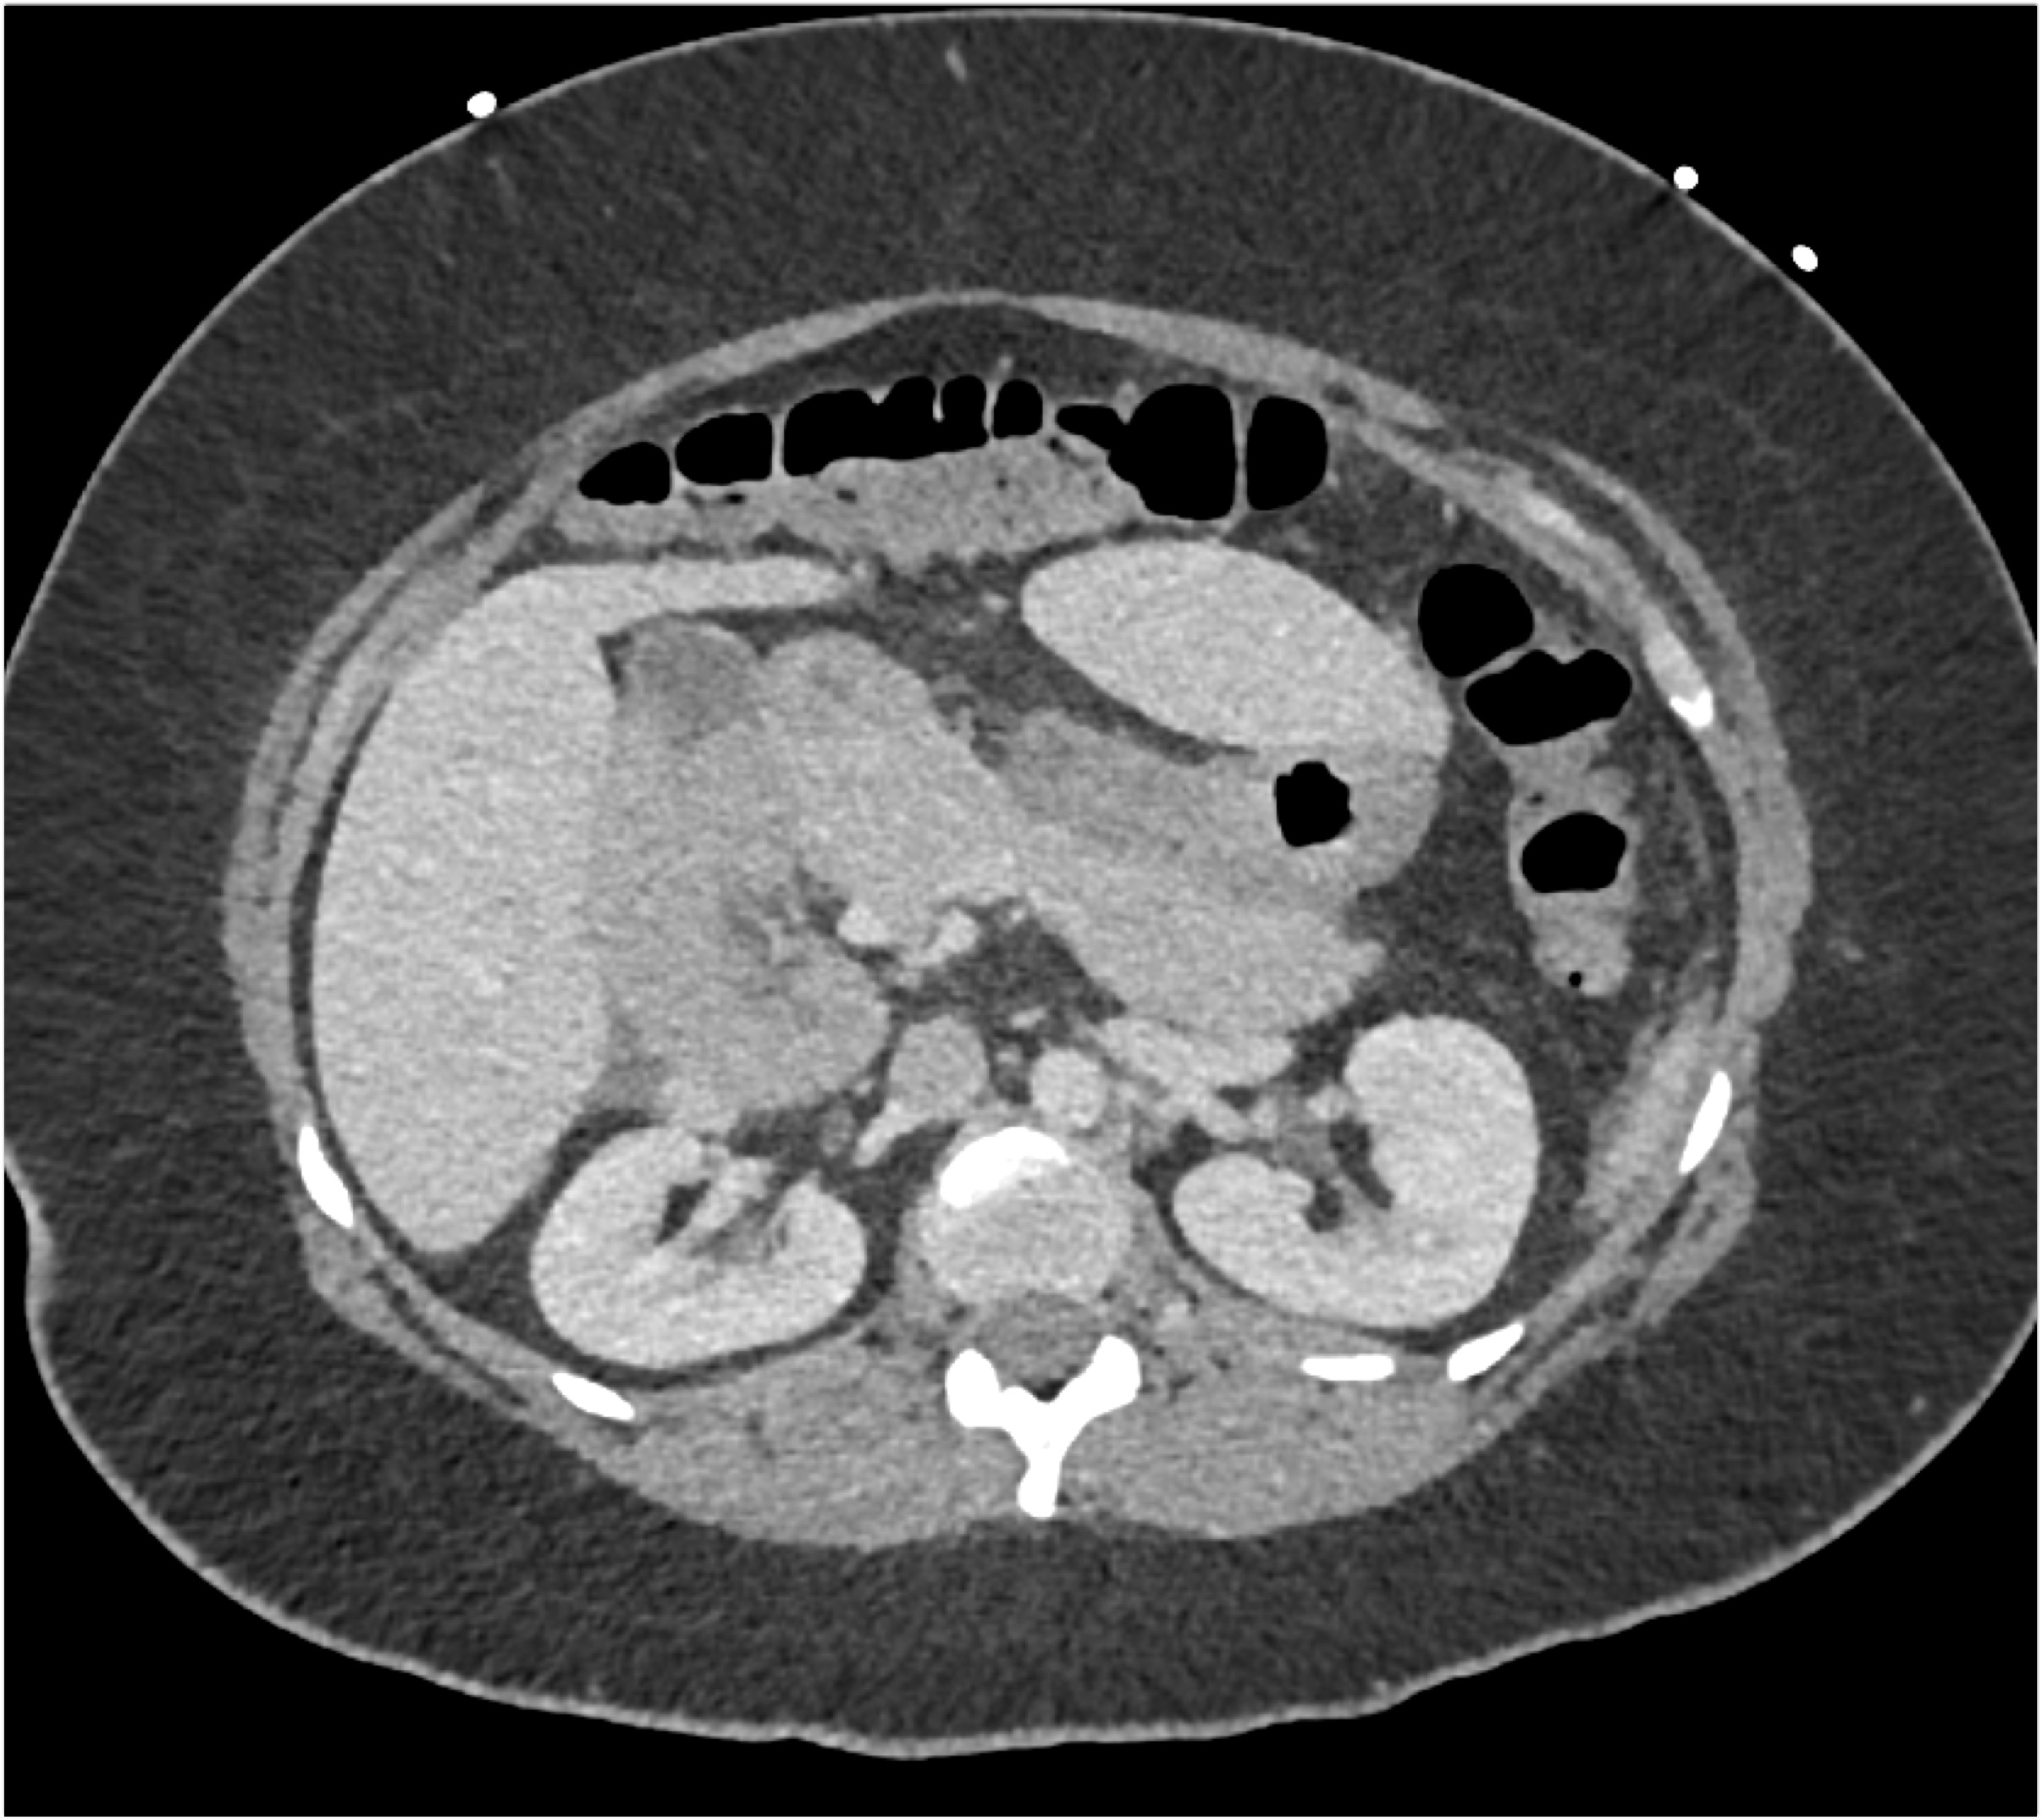

- Evaluate the CT images of each question carefully.

- Take time to make the call on the diagnosis for each individual question.